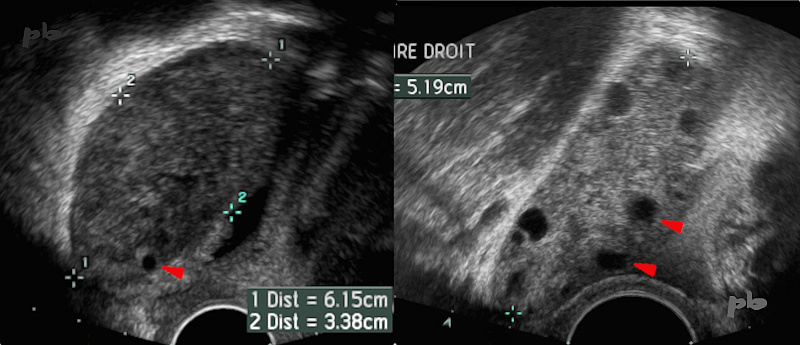

6 – Torsion – Ultrasound

Right adnexal torsion due to a para-tubal cyst. The main ultrasound signs are visible (left image):

– Large ovary (between the crosses: 61 mm in longest diameter)

– Abundant ovarian stroma

– Very few follicles found at the periphery (►)

After surgery and detorsion (right image, taken 12 hours post surgery), follicles reappear, and the ovary size has already decreased (52 mm) with the resolution of edema.